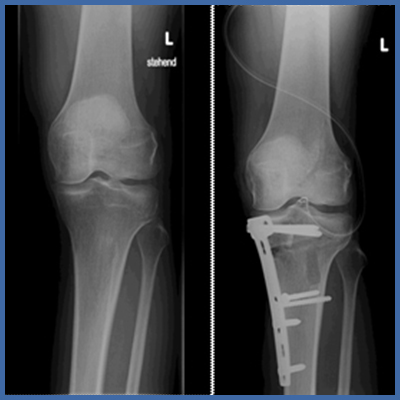

Unter dem Begriff der "Umstellungsosteotomie" versteht man u.a. die operative Korrektur von Achsenabweichungen.

Dieser Eingriff wird bei X-oder O-Beinen angewendet. Ziel der Operation ist es, den durch die Fehlstellung überlasteten Gelenksbereich zu entlasten und die Belastungsachse in den noch gesunden Gelenksabschnitt zu verlagern.

Bild links: Kniegelenk VOR und NACH einer Umstellungsosteotomie.

Das O-Bein hat nun eine gerade Achse.